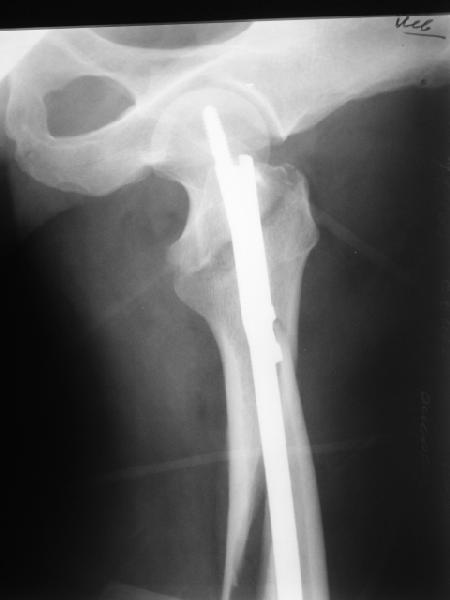

Как раз недавно у меня был примерный случай: больному 36 лет, поступил ночью, травма в результате мотоциклетной аварии, кроме чрезвертельного и спирального перелома левого бедра имеется переломы костей предплечья с этой же стороны. Скелетное вытяжение, а на следующий день больной про оперирован на ортопедическом столе с дистракцией. Чтобы не расколоть чрезвертельный перелом провели временную спицу ближе к переднему кортексу, из малого разреза костодержатель для репозиции, а фиксацию провели антиградным штифтом. Этапы операции на снимках.

Да, сейчас это и у нас самый напрашивающийся выбор. Сделали гвоздем ChM, картинки в приложении.